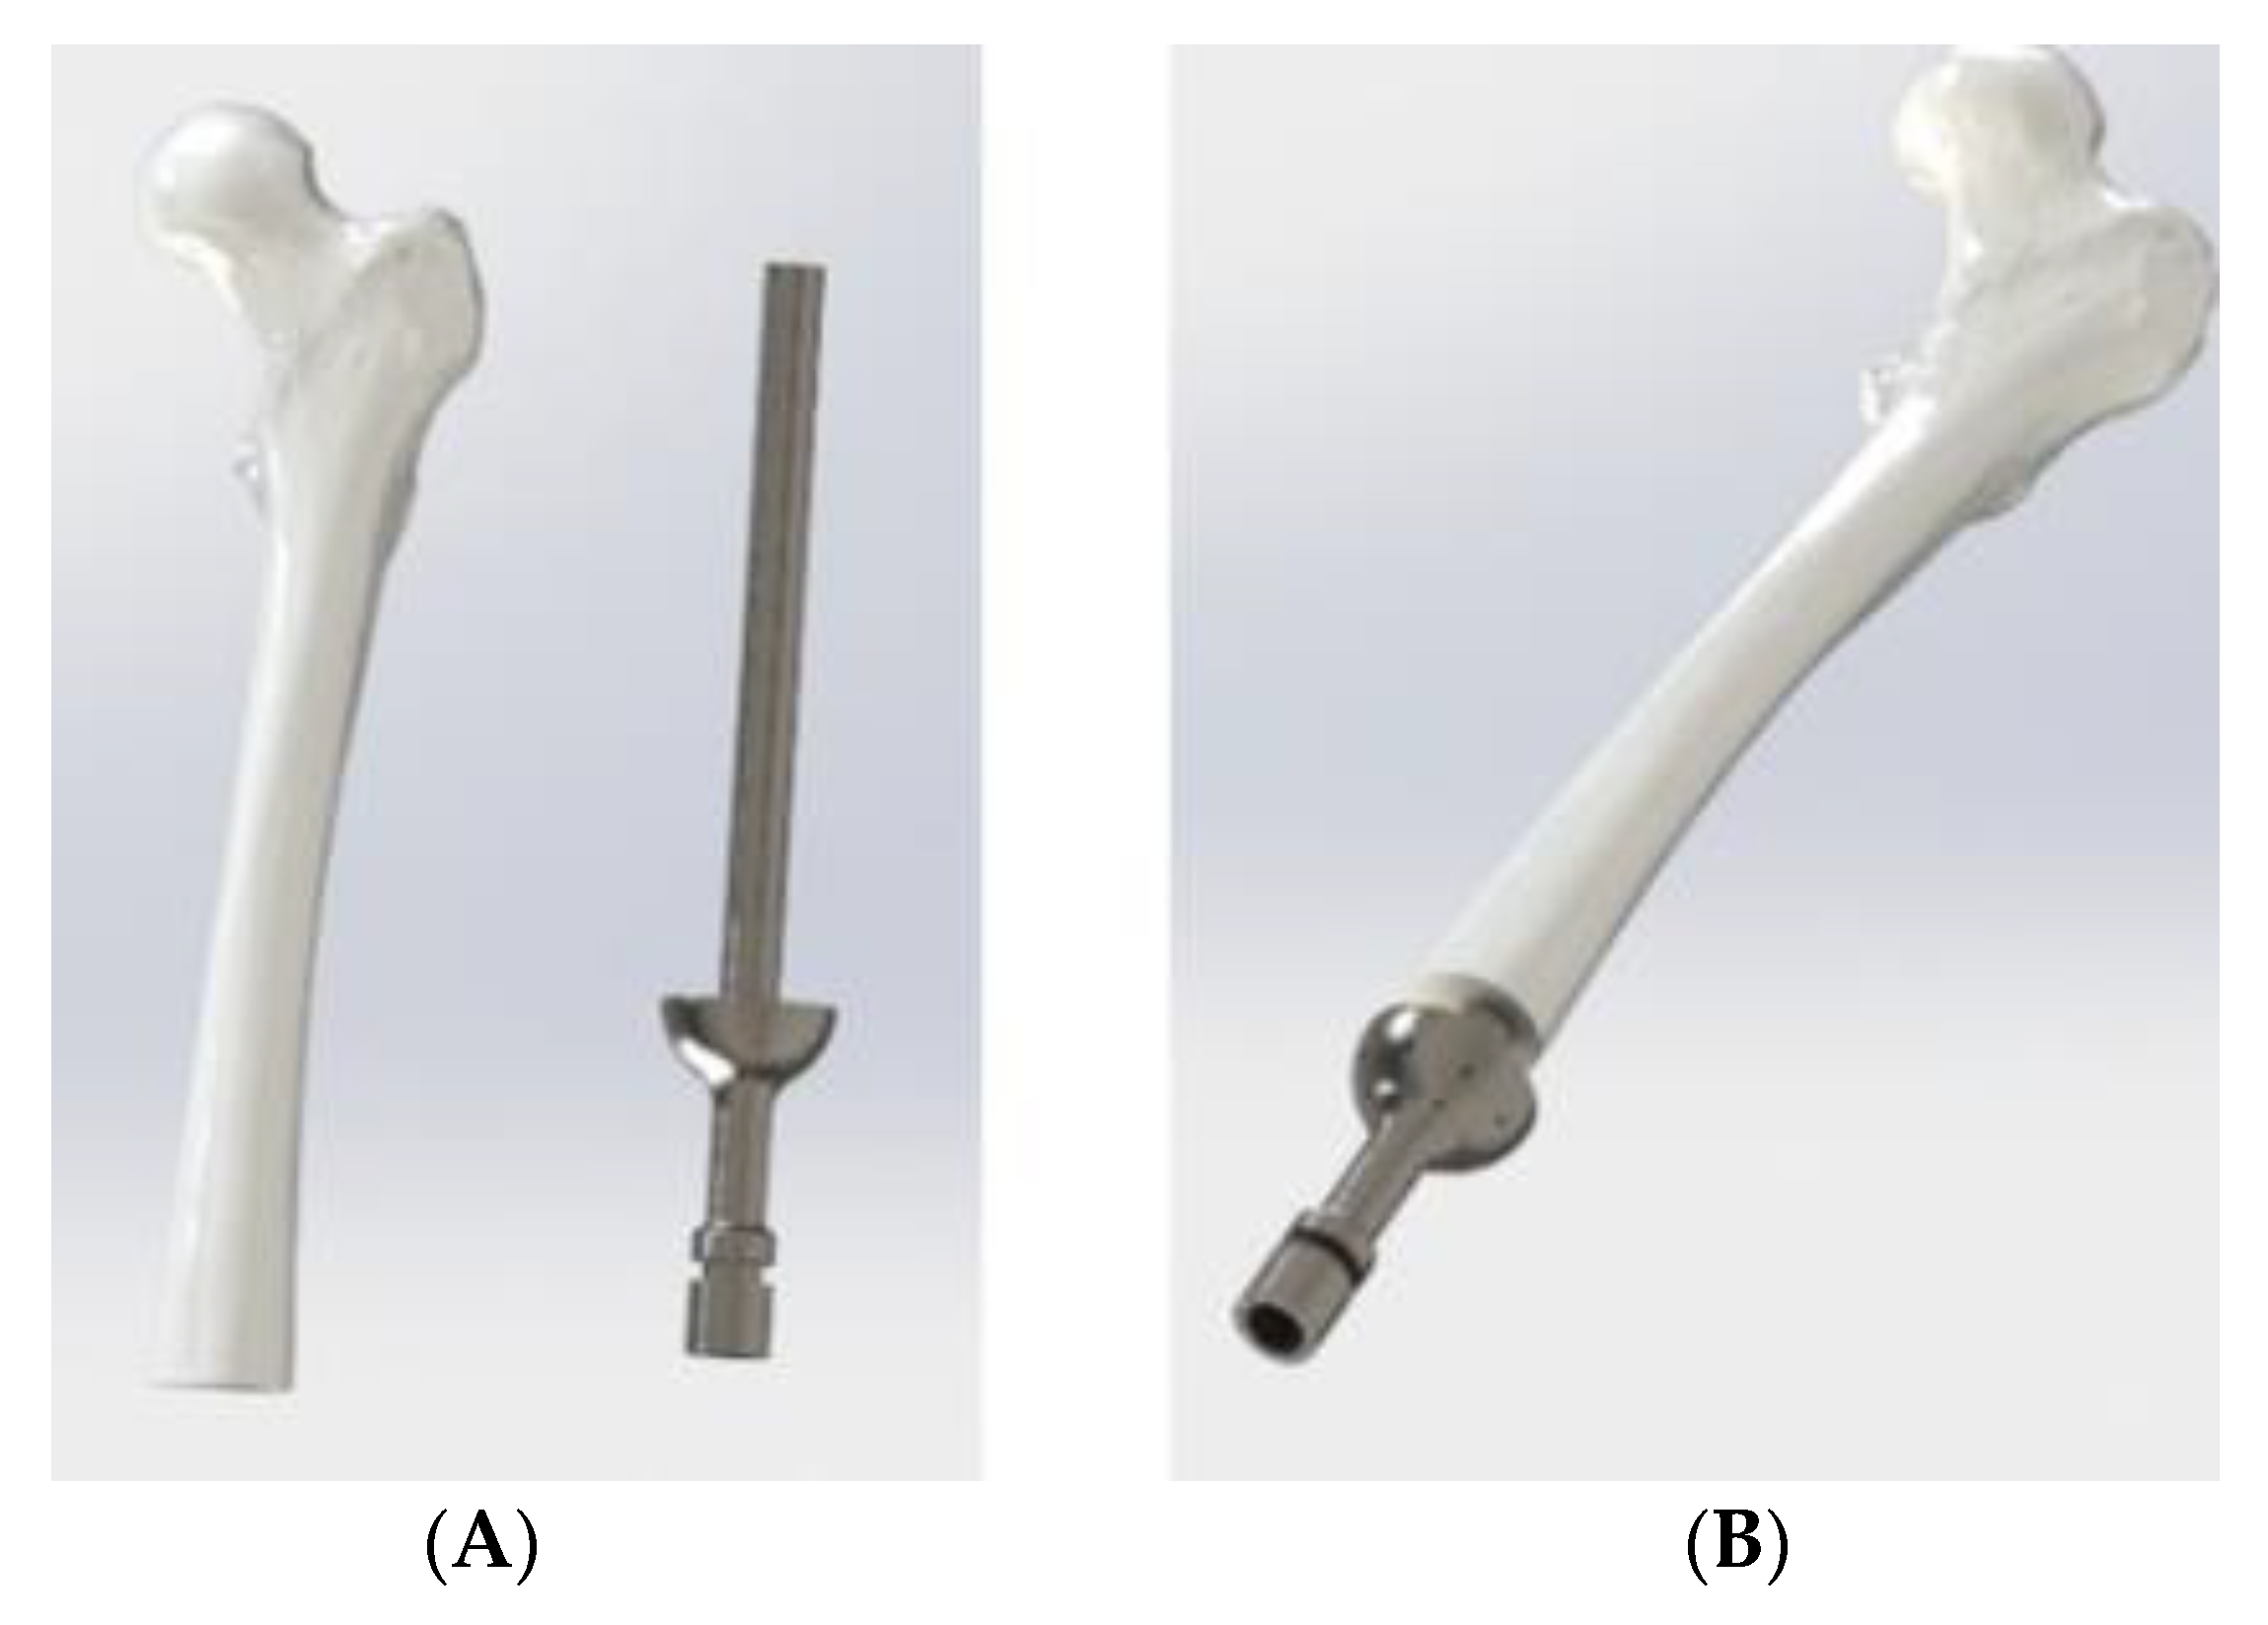

2.1. The Initial Design, Boundary Conditions and Mesh

- The ITAP and femur are both cylindrical, where the femur has an outer diameter of 28 mm and is extruded for 311.5 mm. Whilst there is often a curve in the femur, the tensor faciae latae muscle can reduce the stress acting along the bone and therefore reduce any pronounced stress concentrations acting along the femur [18].

- At one end of the femur there is a 14 mm diameter hole, centred in the middle, cut to a depth of 160 mm.

- The material used for the ITAP has been set as Ti from the ANSYS’s database, this has a σs of 930 MPa and an ultimate tensile stress, UTS, of 1070 MPa. The material selection for the computational modelling is in line with the Ti material used for the ITAP, thus the modelling is a comparable study.

- As the focus of the simulation is on the ITAP, the femur is fixed in place to the pelvis.

- The femur will not be simulated and the free body diagram (FBD) will only consist of the ITAP and the resulting σ is analysed for the impact on the bone anchor.